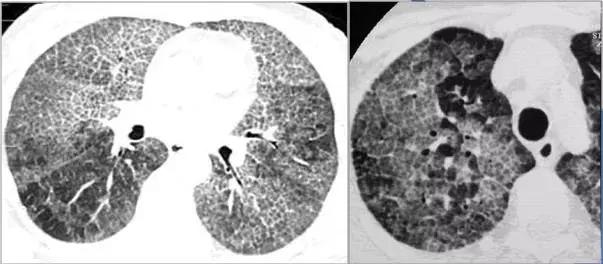

在HRCT上,由于气道疾病或肺血管性疾病引起相邻的肺区血液灌注上的差别而出现的不均匀肺密度区,称马赛克/镶嵌性灌注。常见于造成局部气体滞留或肺实质通气不良疾病中 。

HRCT示略高密度磨玻璃密度影和低密度马赛克灌注区

由于气体储留引起的马赛克灌注

小气道病变引起两侧肺的马赛克灌注

小气道病变引起两侧肺的气体潴留